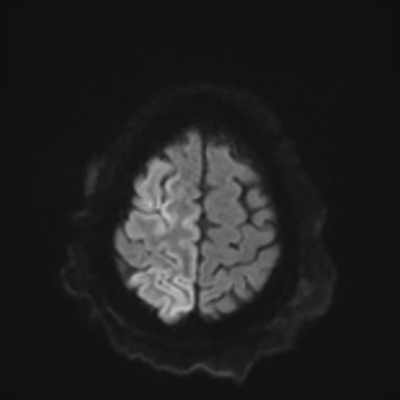

You come back the next day and see how things are going. The patient's electrographic record has shown a moderate encephalopathy (diffuse slowing, disorganization) with frequent right posterior quadrant delta slowing. Based on this result, and an adequately improved clinical examination, you give the okay to proceed with obtaining an MRI of his brain. This is shown below.

MRI brain (DWI)